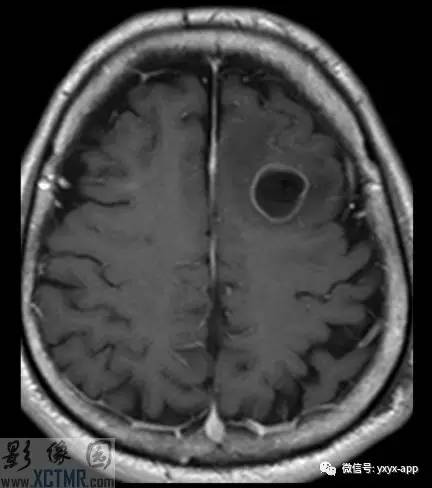

CT:左侧额叶一囊性肿块伴水肿。MRI:轴位T1WI和T2WI显示左侧额叶一囊性肿块伴周围脑实质显著水肿,但无明显占位效应。T1WI增强图显示病变为分叶环形囊状肿块伴周围脑实质水肿,囊壁环形强化,囊内及周围水肿区无强化。

影像学表现取决于感染的位置以及感染的阶段。此病例在胶状水泡阶段,寄生虫的死亡引起明显的炎性反应。影像学表现包括:围绕囊性病变的血管源性水肿;增强后环状增强;T1WI胶状囊性病变周围为低信号;有时可见T1WI头节高信号影。